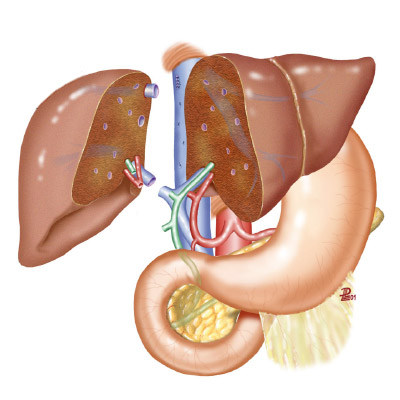

RECHERCHE TRANSLATIONNELLE

Le groupe Hospital Clínic a une longue tradition de recherche qui le place au rang des institutions jouissant d'une reconnaissance internationale. La recherche translationnelle et son application dans le cadre de la recherche clinique jouent un rôle essentiel dans la réputation de barnaclínic+.

SOINS CLINIQUES DE POINTE

L’activité clinique est exercée de manière exhaustive au sein d’unités et d’équipes interdisciplinaires appliquant des protocoles et processus de qualité s’appuyant sur les meilleurs éléments scientifiques disponibles.